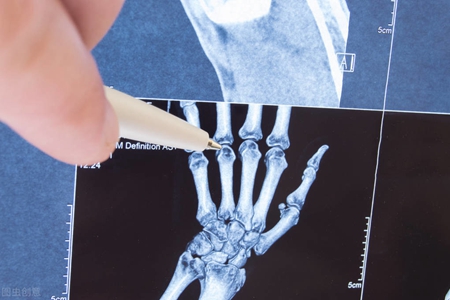

类风湿关节炎是因为人体内免疫系统发生功能紊乱,导致全身大大小小的关节出现肿胀、疼痛,尤其是双手的关节会出现肿胀、疼痛、僵硬。未得到有效、正确治疗的人群中,80%以上患者因关节畸形而残疾,丧失劳动能力甚至生活自理能力。